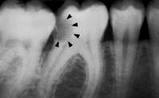

La información radiográfica contribuye significativamente a los hallazgos clínicos en términos del hallazgo de lesiones en diferentes estadíos de progresión (29,32) Las radiografías ayudan a estimar la profundidad de desmineralización por caries en el esmalte y la dentina. La profundidad no siempre está asociada con la presencia de cavidad de caries, en especial en superficies proximales.

Investigaciones clínicas que se realizaron en un país con una tasa baja de progresión de caries revelaron que, en promedio, el 32% de las lesiones visibles radiográficamente que se extendían hasta el tercio externo de la dentina no  había cavidad de caries; por el contario, el 72% de las lesiones que se extendían hasta 2/3 partes de la dentina tenían cavidad de caries (33) Las lesiones con cavidad de caries clínicamente o las lesiones con obvia radiolucidez en dentina (más profunda que el 1/3 externo) en la superficie oclusal están altamente infectada la dentina, debajo de la unión amelo-dentinaria (34,35)

La evidencia indica que la profundidad de penetración radiográfica en la que se puede predecir de forma confiable que la superficie del diente está cavitada y que la dentina está muy infectada, es cuando la radiolucidez está más alla del tercio externo de dentina (7,34,35,38,40). Esto corresponde a los códigos 4, 5 y 6 en el sistema de clasificación radiográfica de ICCMS. Ver tabla 6. En casos en que las tasas de progresión son rápidas, se puede esperar que en lesiones con clasificación 3 en el sistema descrito anteriormente, haya formación de cavidad.